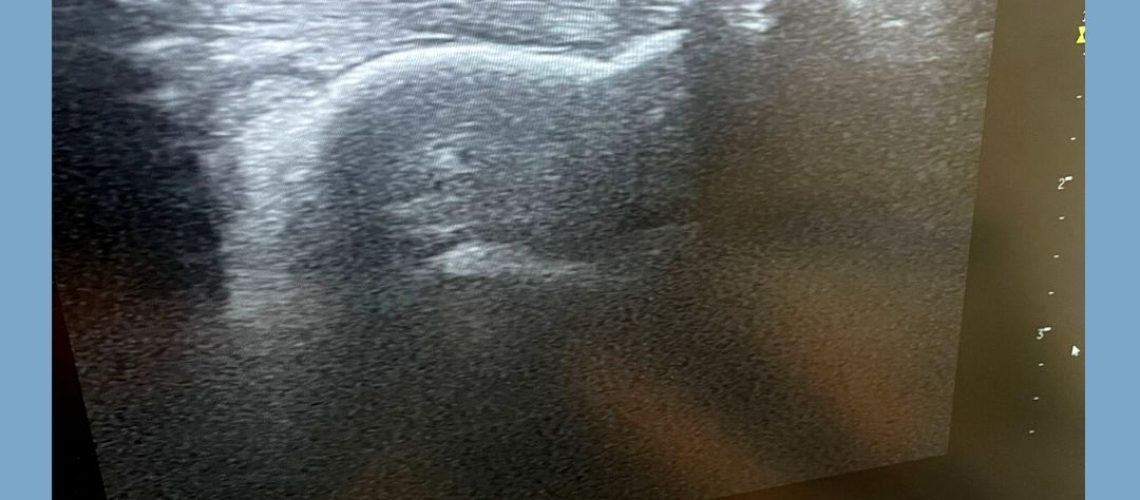

En el post de hoy os muestro como he tratado la calcificación en el Tendón de Aquiles en un paciente, el cual ha reducido hasta un 70% el dolor tras su primer tratamiento en la clínica ✅

Desliza la imagen para ver como se visualiza en nuestro ecógrafo 😊➡️